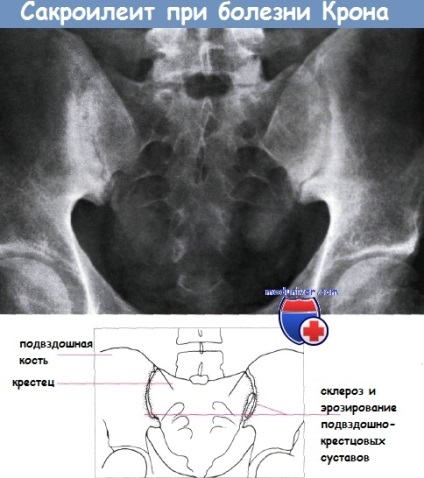

Sacroiliitis și spondilita anchilozantă adesea asociată cu colita ulcerativa, deși există în boala Crohn. Fistula in boala Crohn apar după o intervenție chirurgicală sau spontan. In particular, enteric cutanat fistula este mai frecventă la cicatrice postoperatorie. fistula internă include orice combinație a intestinului subțire și gros unele cu altele, si vezica urinara si vagin. fistulei perianale este discutată într-un articol separat pe acest site. În ciuda faptului că, în unele cazuri, un tratament cu azatioprină sau infliximab, multe fistule necesită intervenție chirurgicală.

semne radiologice patognomonice ale bolii Crohn au, modificări pot fi cauzate de alte boli inflamatorii intestinale - tuberculoza, iersinioza. Diagnosticul se bazează pe o combinație de imagini cu raze X cu clinice, de laborator și tehnicile histologice. Atunci când este diagnosticată cu ultrasunete îngroșarea caracteristică a peretelui intestinal și modificarea răspunsului acustic al straturilor normale, se poate detecta zonele cu stenoza rd dilatarea anterioară. O astfel de cercetare este adesea neglijat, în ciuda faptului că oferă informații de diagnosticare valoroase, și poate fi utilizat pentru a identifica complicatii asociate, cum ar fi abcese.